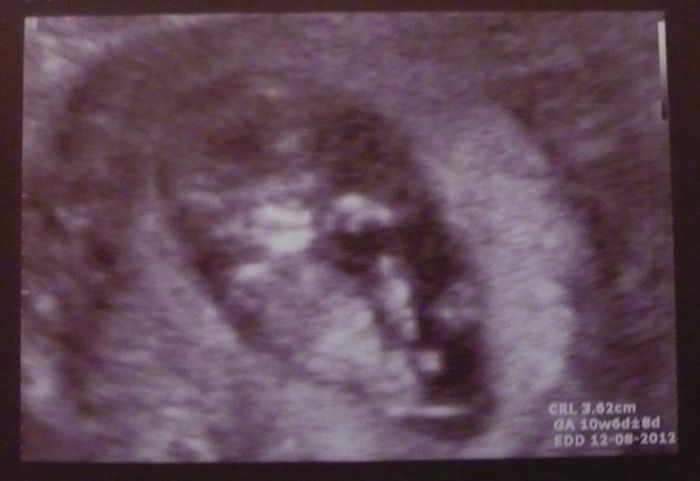

Ahoj holky...tak ten dnešní screening mám i nemám za sebou. Sice se mi na mimčo dr. podíval, ale bez krevních testů mi k tomu zatím nemohl nic říct a na ty jdu příští týden a až potom na ten screening. Nicméně ufounek odpovídá těm 10+5, ve kterém jsem a na první pohled nenašel žádnou anomálii. Bylo krásný se na maličkého dívat. I mého muže to uplně dojalo :-)